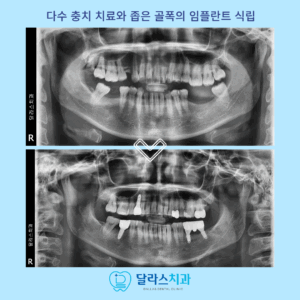

노원치과 하악 좁은 골폭의 전치부에 최신4세대 Ari 임플란트를 식립한 사례

노원치과 하악 좁은 골폭의 전치부에 최신4세대 Ari 임플란트를 식립한 사례   안녕하세요 노원치과 달라스치과입니다.   임플란트는 치아 상실 시 기능과 심미를 동시에 회복할 수 있는 대표적인 치료 방법입니다. 하지만 모든 부위에 식립하는 임플란트가 동일한 난이도를 보이는 것은 아니며 여러 부위 더보기…